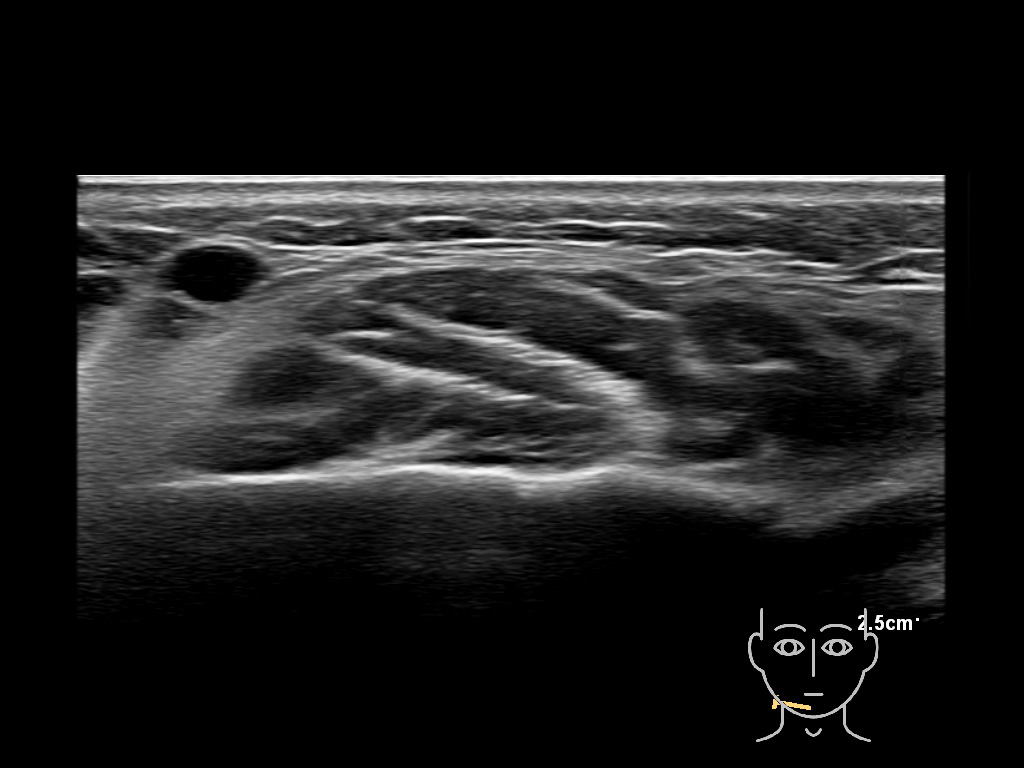

Filler deposits may end up unintentionally in the SMAS or fascial layers of the skin. Very often this will not lead to adverse events, however, adverse events ( nodules, migration / redistribution impaired muscle movement and smiling and malar edema) are are often related to filler ending up in the SMAS or fascia.

Study the first image to recognize the different layers. If you are sure about the layers, swipe to the second image to view the answer (if applicable).